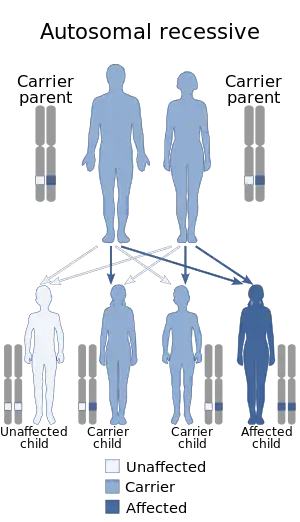

Aromatase deficiency is an exceedingly rare condition characterized by extremely low levels or complete absence of the enzyme aromatase activity in the body.[2] It is an autosomal recessive disease resulting from various mutations of gene CPY19 (P450arom) which can lead to delayed puberty in females, osteoporosis in males and virilization in pregnant mothers. As of 2016, only 35 cases have been described in medical literature.[3]

Aromatase deficiency is an autosomal recessive disease with most of the mutations occur along the highly conservative regions of the gene. Both homozygous and heterozygous mutations have been identified along various location of the exon on the P450 arom (CYP19) gene localized on chromosome15p21.1.[8] In addition, mutations in cytochrome P450 oxidoreductase (POR), which is required for enzymatic activity of aromatase, can also cause aromatase deficiency.[10]